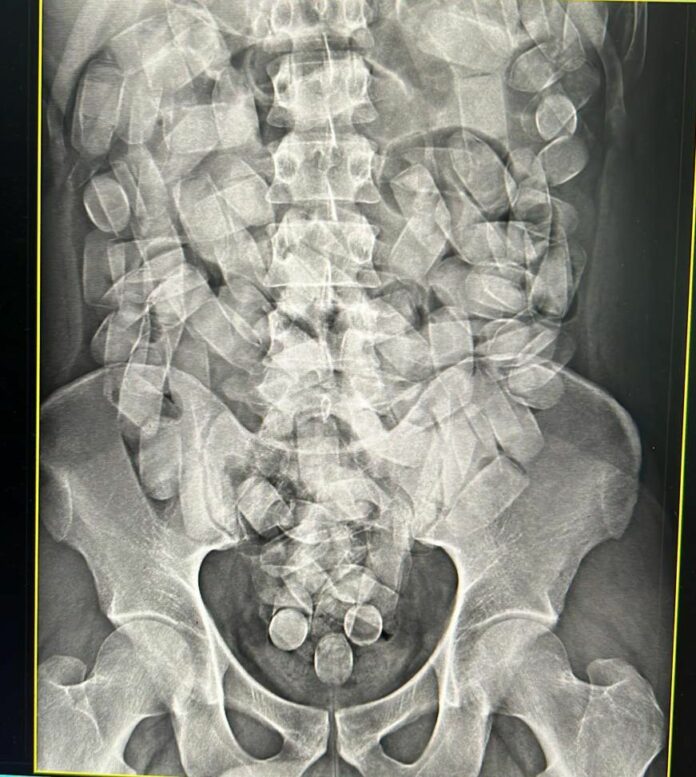

Em nota sobre a ocorrência, a PF cita que o autor passou pelo aparelho de raio-x, que constatou a existência de 125 cápsulas com cocaína no estômago.